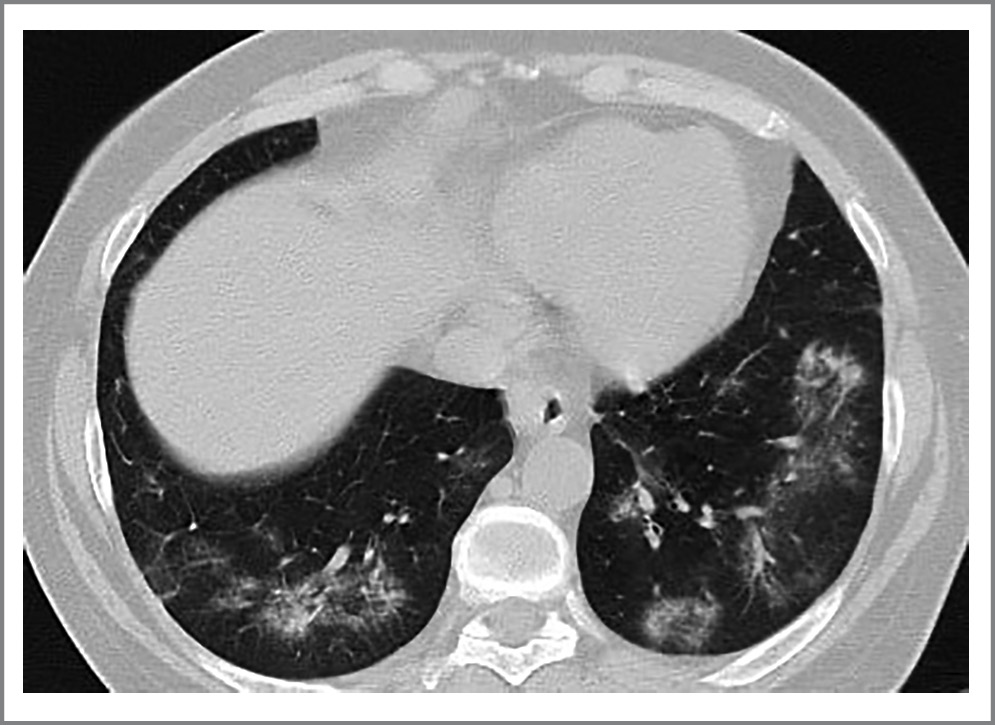

Пациент Ч., 64 года, постоянно проживает в Москве, пенсионер, ранее работал спортивным тренером. В анамнезе сахарный диабет 2-го типа, в течение последних 2 лет получает комбинированную инсулинотерапию. Пациент 8 января 2021 г. отметил повышение температуры тела до 39°С, появление одышки, снижение сатурации до 89%, потерю вкуса и обоняния. Госпитализирован в ГБУЗ ГКБ №40 в Москве. Выполнена компьютерная томография (КТ) грудной клетки – выявлены признаки двусторонней полисегментарной пневмонии, объем поражения легких до 50% (КТ-2), получен положительный тест методом полимеразной цепной реакции (ПЦР) на новую коронавирусную инфекцию. В анализах крови при поступлении отмечено повышение СРБ до 112 мг/л (0–5), снижение лимфоцитов до 0,5×109/л (1–3,7), повышение D-димера до 570 мкг/мл (0–250). Пациенту проводилась терапия антикоагулянтами, ГКС, ингибитором интерлейкина-6 (тоцилизумаб), фавипиравиром, кислородотерапия через носовые канюли (4–5 л/мин). На фоне терапии отмечались положительная клиническая динамика, нормализация гемодинамических и биохимических показателей крови, уменьшение жалоб, получен отрицательный ПЦР-тест на COVID-19. В конце января 2021 г. пациент выписан на амбулаторное долечивание, ГКС и антикоагулянты не получал. С середины февраля 2021 г. у больного повторно отмечались повышение температуры до 39°С, снижение сатурации до 75%, после чего госпитализирован в частную клинику с диагнозом внебольничной пневмонии и подозрением на тромбоэмболию легочной артерии. При КТ органов грудной клетки выявлены признаки двусторонней полисегментарной пневмонии, объем поражения легких более 75% (КТ-4). В анализах крови отмечалось повышение СРБ – до 236 мг/л (0–5), интерлейкина-6 – до 20,9 пг/мл (0–7), D-димера – до 5,65 мкг/мл (0–0,5), повторно получен отрицательный ПЦР-тест на новую коронавирусную инфекцию. Получал терапию антибиотиками и системными ГКС, кислородотерапию. Учитывая клиническую картину, данные КТ, больной переведен в госпиталь для лечения новой коронавирусной инфекции. Продолжена терапия ГКС (дексаметазон) и антибиотиками, а также назначены антикоагулянты и кислородотерапия. В результате проводимого лечения отмечались положительная динамика, нормализация анализов крови, уменьшение жалоб. По данным КТ – положительная динамика, уменьшение поражения легких до 50–75% (КТ-3). Выписан в начале марта с улучшением, терапия на амбулаторном этапе не назначалась. Через 2 нед после выписки – повторное появление жалоб на выраженную одышку, снижение сатурации до 90–92%, госпитализирован в Клинику им. Е.М. Тареева. В анализах крови выявлено повышение СРБ до 375 мг/л (0–5). По данным КТ органов грудной клетки выявлены уплотнения легочной ткани по типу «матового стекла» (рис. 2), выполнены исследование функции внешнего дыхания и диффузионный тест, выявлено снижение DLCO cor (гемоглобин 118 г/л) до 43% и форсированной жизненной емкости легких до 64%, объема форсированного выдоха за 1-ю секунду – до 68%.

Рис. 2. КТ грудной клетки пациента от 07.04.2021. / Fig. 2. Computer tomography scan of the patient's chest from 04/07/2021.